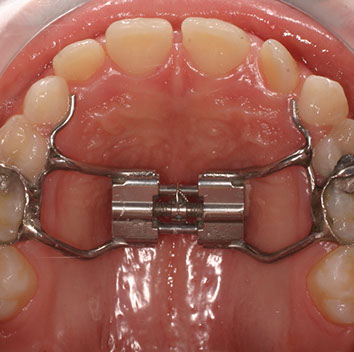

Talvolta, quando si vuole espandere l’arco palatino iposviluppato,  può essere necessario applicare un Diastasatore